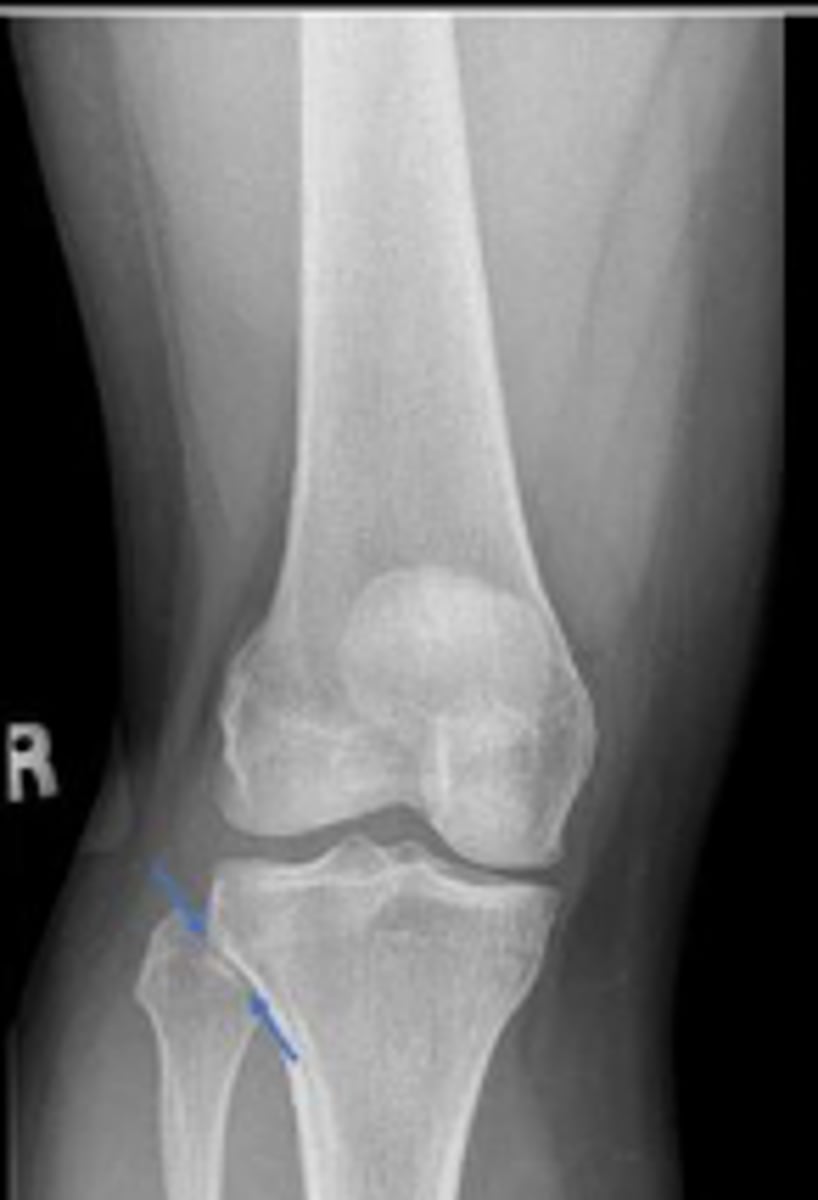

Right internal oblique knee

What is the name of the radiographic view?

Right proximal tibiofibular joint space

What space are the arrows pointing to?

Head of the right fibula

What is outlined?

Neck of the fibula

What are the blue arrows pointing to?

Lateral collateral ligament

What inserts at the location of the blue arrows?

Lateral collateral ligament avulsion fracture of

the right knee

What is the most significant radiographic finding?